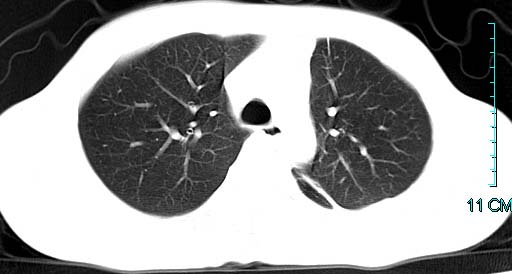

以下是引用ctkz987在2006-3-28 13:04:00的发言:[br]左侧胸腔积液穿刺后多发气液平(多房性),结合临床有高热不除外合并感染。

以下是引用qian在2006-3-28 14:32:00的发言:[br]左肺下叶大片状阴影,密度不均,见有条片影和空洞及气液平,少量胸腔积液伴有胸膜增厚,从图像看积液密度比水的密度高,结合病史,考虑左下肺化脓性炎症伴有脓胸。

以下是引用wawaquan在2006-3-28 22:25:00的发言:[br]左上肺舌段多发斑片影。结合“男24y咳嗽咳痰气促伴高热(38.5--39.5)20多天”及穿刺史,[br]考虑1 左下肺化脓性炎症;2脓胸。

以下是引用乡医在2006-3-28 18:37:00的发言:[br]左侧多发液气平面结合患者男24y咳嗽咳痰气促伴高热(38.5--39.5)20多天,查胸水:ldh239.3,总蛋白59.19,tb-ab阴性,利凡它试验+,红c2.7*109,白c1.08*109,分类淋巴92%分叶8%,考虑1脓胸2肺隔离征感染